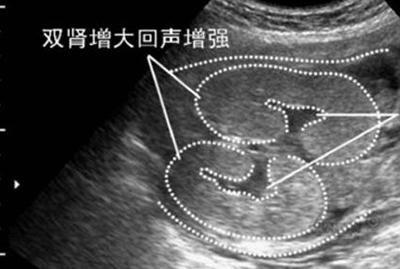

3.如果B超单子有出现肾孟扩张90%或者分离,十有八九就是男宝宝了。当胎儿憋尿时,就会发生肾盂分离,因为在一个医学杂志里说过,90%的肾盂分离发生在男宝身上,通常出生的时候都会拉泡尿解决这个问题。因此如果你的B超单子上有肾盂分离,说明男宝的概率远远大于女宝。

男宝不一定会肾盂分离,肾盂分离很大可能就是男宝,方法很简单,赶紧拿起B超单子看看吧。希望各位准妈妈都能得偿所愿。